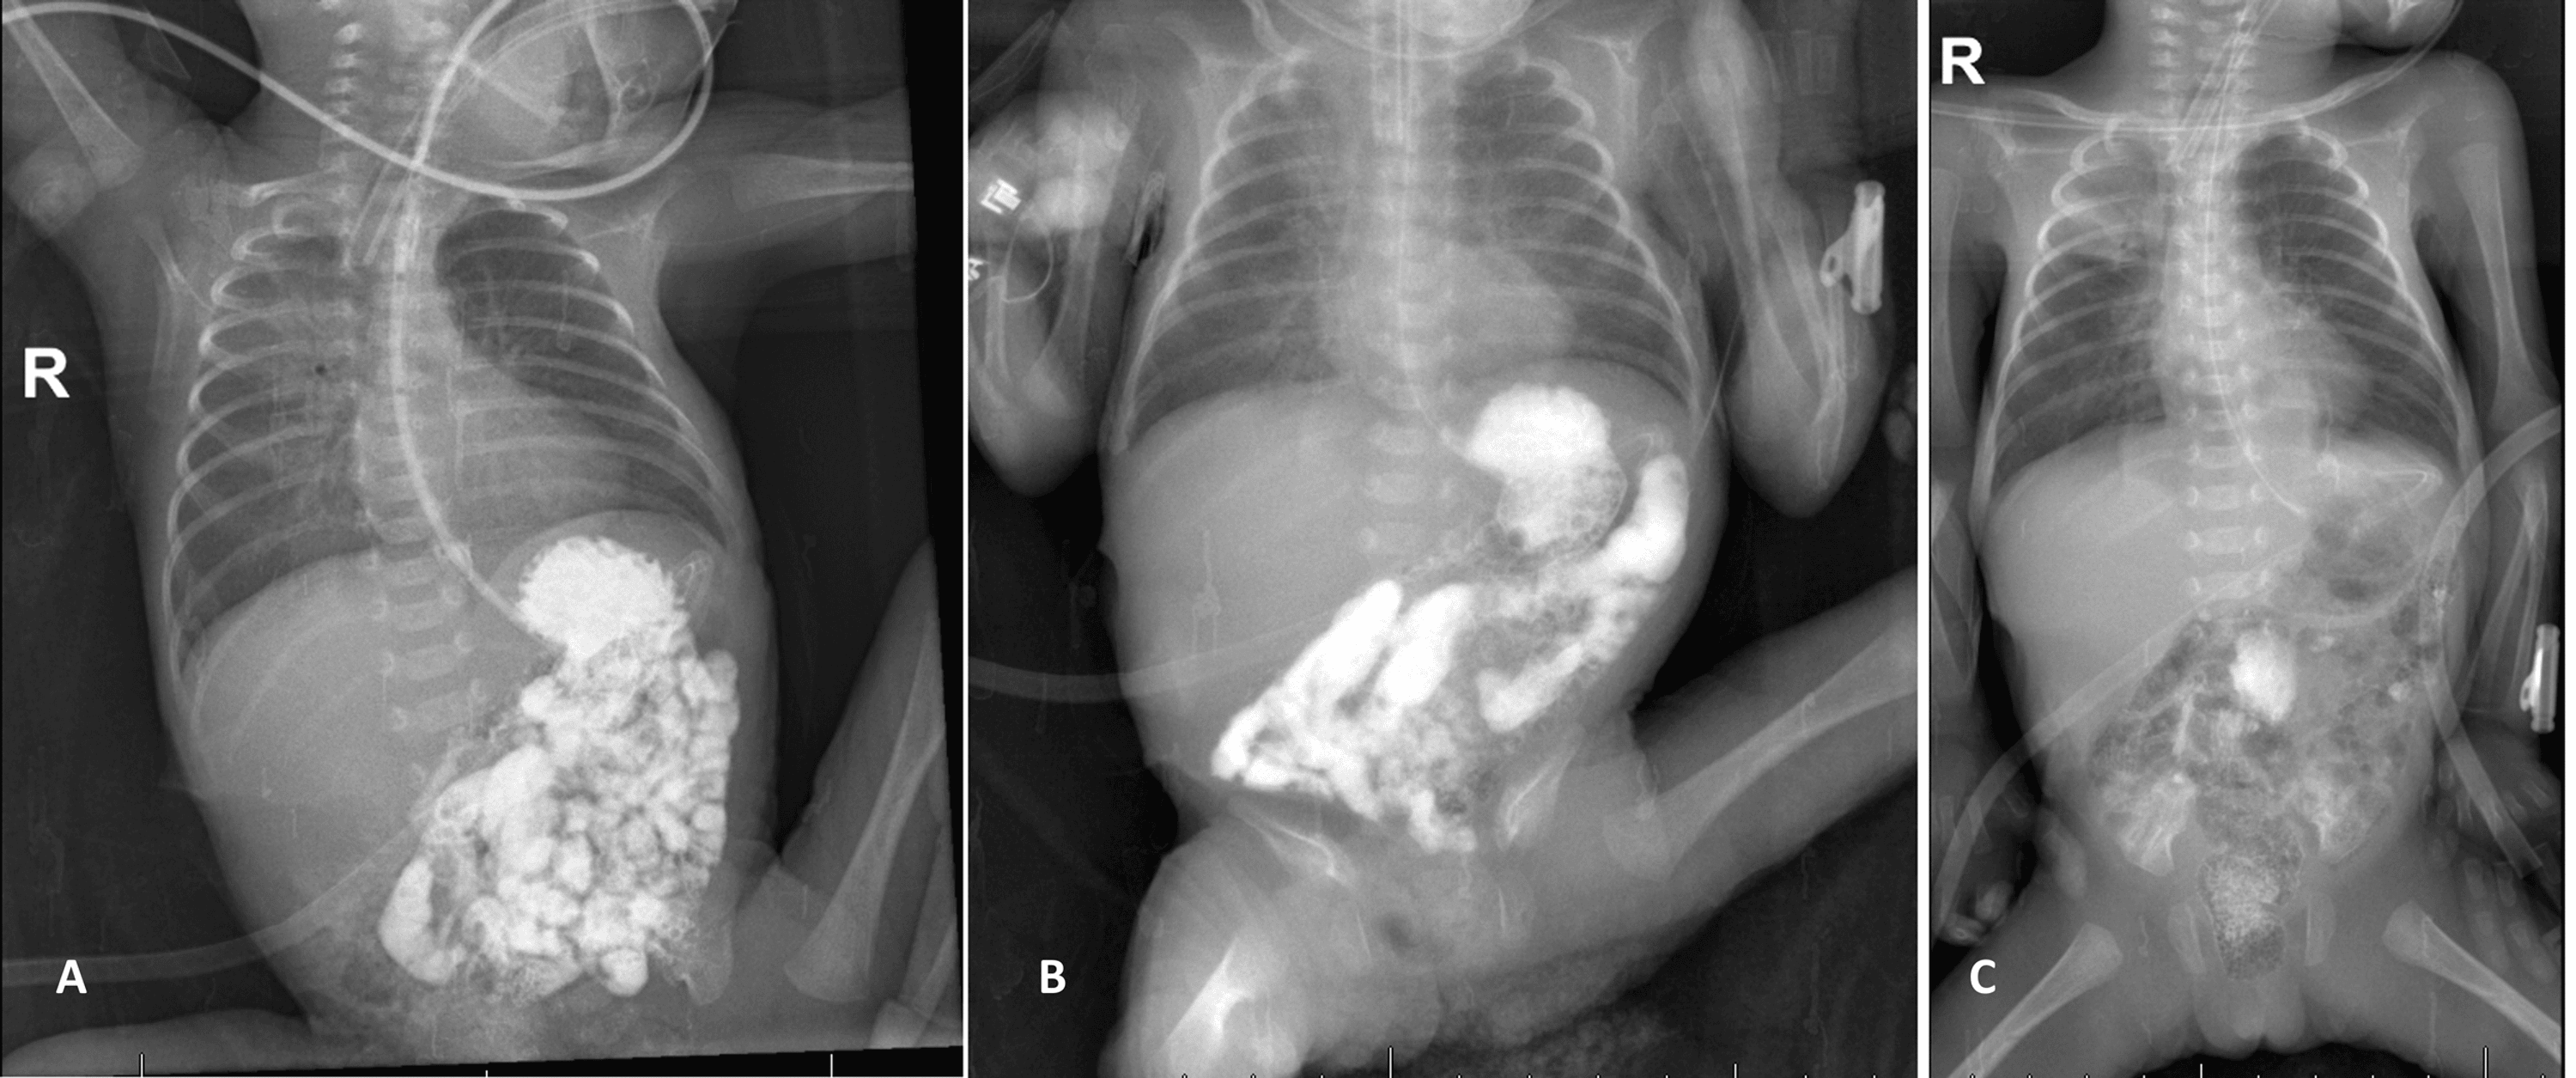

Meconium obstruction of prematurity Siddiqui et al. ADC Fetal Intestinal Blockage In Premature Babies Small bowel atresia, also known as intestinal atresia, is a birth defect that affects a part of the small intestine, the tube that connects the. Intestinal obstructions are the most common surgical emergencies in the neonatal period. Children's minnesota treats intestinal atresia in babies. We report a premature (32 weeks) newborn who developed acute onset symptoms of small. Discover intestinal. Intestinal Blockage In Premature Babies.

Human milk fortifier An occult cause of bowel obstruction in extremely Intestinal Blockage In Premature Babies Children's minnesota treats intestinal atresia in babies. We report a premature (32 weeks) newborn who developed acute onset symptoms of small bowel obstruction in 3 rd week of life, and discuss the. Intestinal obstructions are the most common surgical emergencies in the neonatal period. Recent estimates place the incidence at 1 in 2000 live births. Discover intestinal atresia types, including. Intestinal Blockage In Premature Babies.

Figure 1 from Intussusception in a Premature Neonate A Rare Often Intestinal Blockage In Premature Babies We report a premature (32 weeks) newborn who developed acute onset symptoms of small. Recent estimates place the incidence at 1 in 2000 live births. Small bowel atresia, also known as intestinal atresia, is a birth defect that affects a part of the small intestine, the tube that connects the. We report a premature (32 weeks) newborn who developed acute. Intestinal Blockage In Premature Babies.

(PDF) Intestinal obstruction in a premature baby Endoscopic diagnosis Intestinal Blockage In Premature Babies We report a premature (32 weeks) newborn who developed acute onset symptoms of small bowel obstruction in 3 rd week of life, and discuss the. Small bowel atresia, also known as intestinal atresia, is a birth defect that affects a part of the small intestine, the tube that connects the. Bowel obstruction is one of the most common surgical emergencies. Intestinal Blockage In Premature Babies.

(PDF) Intussusception in Premature Baby Unusual Cause of Bowel Intestinal Blockage In Premature Babies Discover intestinal atresia types, including jejunal atresia, & treatment for blocked intestines. Recent estimates place the incidence at 1 in 2000 live births. Small bowel atresia, also known as intestinal atresia, is a birth defect that affects a part of the small intestine, the tube that connects the. We report a premature (32 weeks) newborn who developed acute onset symptoms. Intestinal Blockage In Premature Babies.

Multiple sequential intussusceptions causing bowel obstruction in a Intestinal Blockage In Premature Babies Intestinal obstructions are the most common surgical emergencies in the neonatal period. Discover intestinal atresia types, including jejunal atresia, & treatment for blocked intestines. We report a premature (32 weeks) newborn who developed acute onset symptoms of small bowel obstruction in 3 rd week of life, and discuss the. Bowel obstruction is one of the most common surgical emergencies in. Intestinal Blockage In Premature Babies.